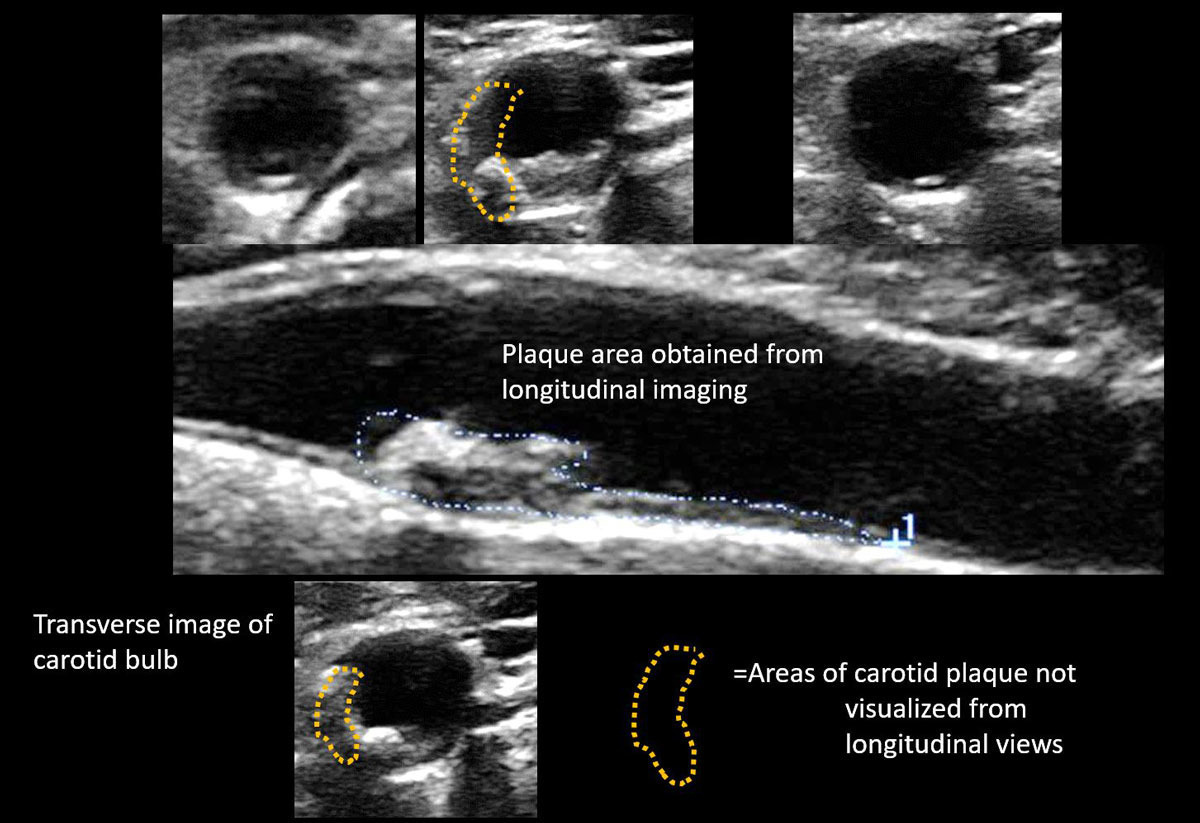

- 경동맥 플라크(atheromatous plaque): 초음파 영상에서 관찰되는 지방침착물로, 단단한 석회화 플라크는 혈관 내피를 손상시키고 혈전 형성을 유발할 수 있습니다.

결과지에는 혈류 속도, 혈류 방향, 플라크의 형태 및 위치 등이 함께 기재됩니다. 영상 분석을 통해 플라크의 안정성 여부를 평가하면 향후 뇌졸중 위험 예측에도 도움이 됩니다.